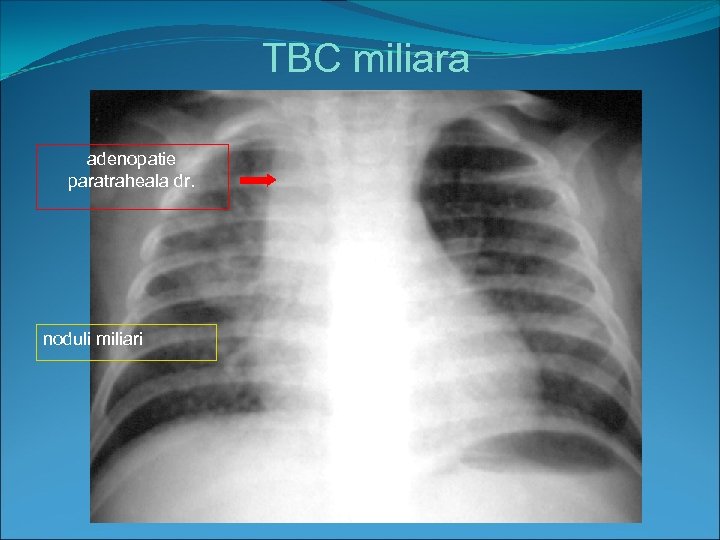

Forme complicate 1. tuberculoza miliara • este o diseminare limfo-hematogena • Rx-multiple opacitati miliare , cu un diametru sub 3 mm; opacitatile miliare sunt foarte greu de evidentiat radiologic si sunt mai bine vizibile pe radiografia de profil datorita fenomenului de sumatie sau pe CT • 2. granulia( forma generalizata de TBC ce afecteaza diferite organe si determina meningita, pericardita, atingeri uro-genitale etc • 3 forme bronhopneumonice. fistulizarea ganglionilor in bronsie determina aparitia de forme bronhopneumonice cu opacitati alveolare diseminate bilateral

TBC miliara adenopatie paratraheala dr. noduli miliari